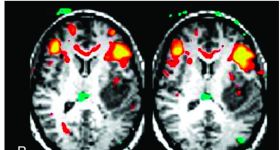

我們都知道,在功能磁共振研究中,我們最感興趣的是從血流動力變化中觀察到灰質(zhì)也就是神經(jīng)元活動是如何表征的,在...